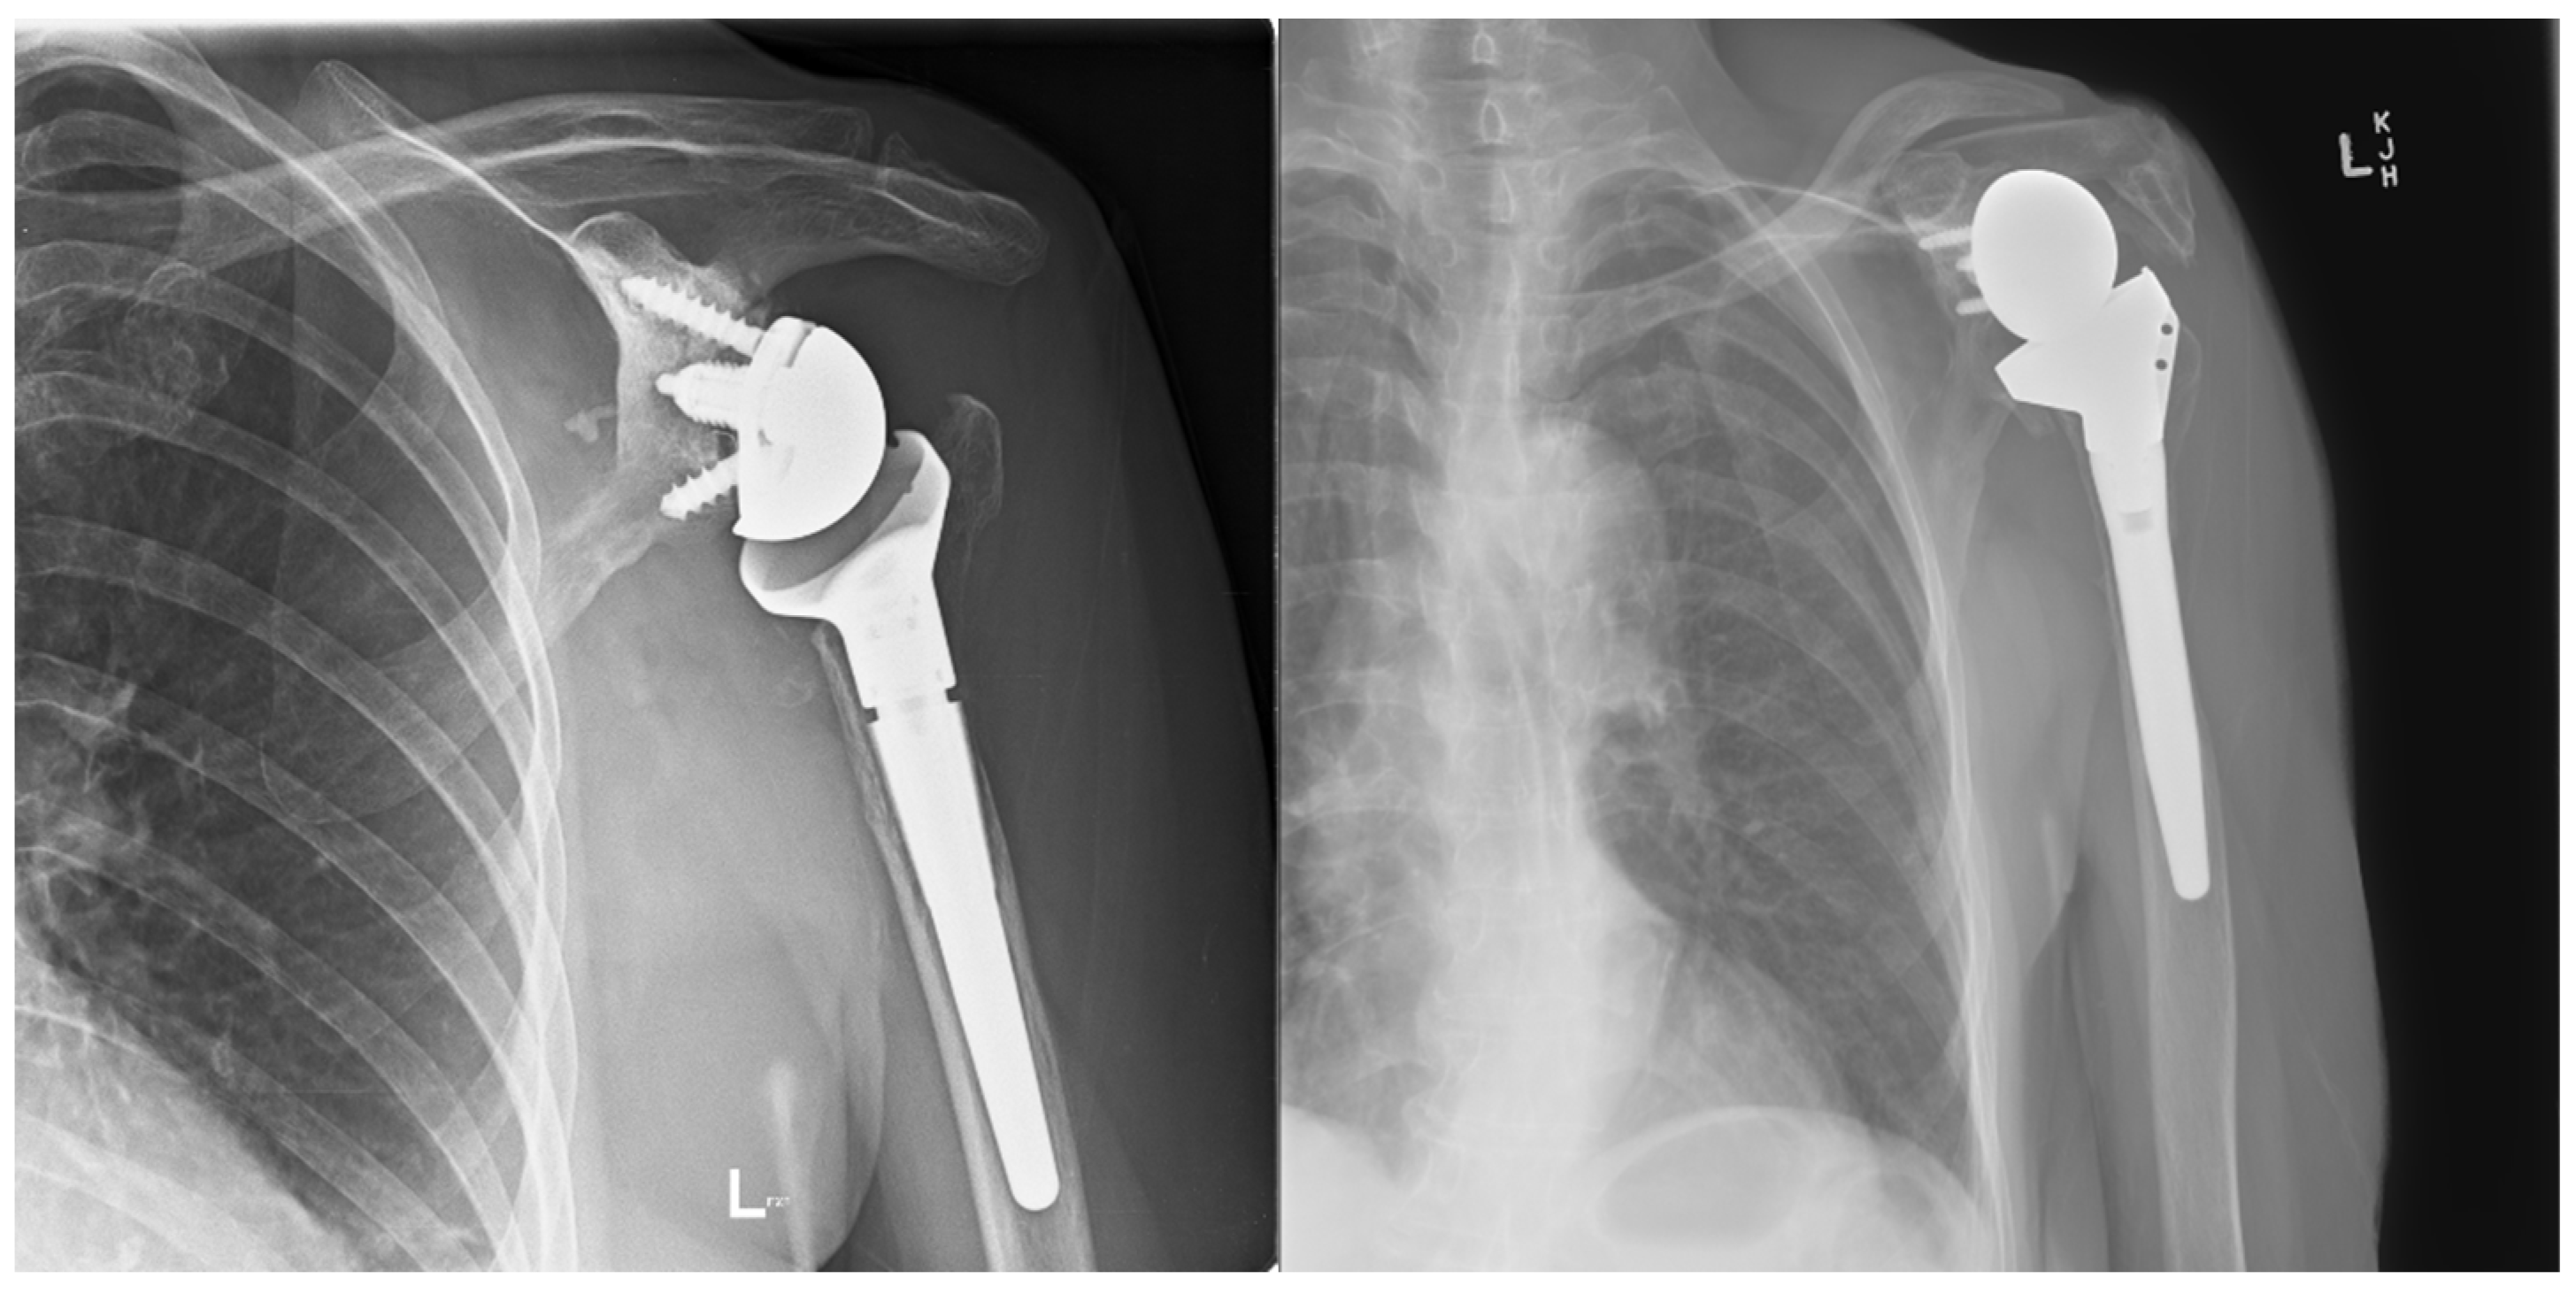

4.2. Radiologic Follow-Up

Two patients had repeat CT scans at two years, and one had X-ray at four years, showing complete graft union and no osteolysis (Figure 8). As mentioned, one patient was lost to follow-up, and another refused follow-up imaging.

Figure 8.

(a) Preoperative anteroposterior (AP) X-ray showing bone loss on the proximal humerus; (b) immediate postoperative AP X-ray showing reconstruction of the proximal humeral defect using an APC; (c) coronal CT scan showing union of the APC with the native humeral shaft.